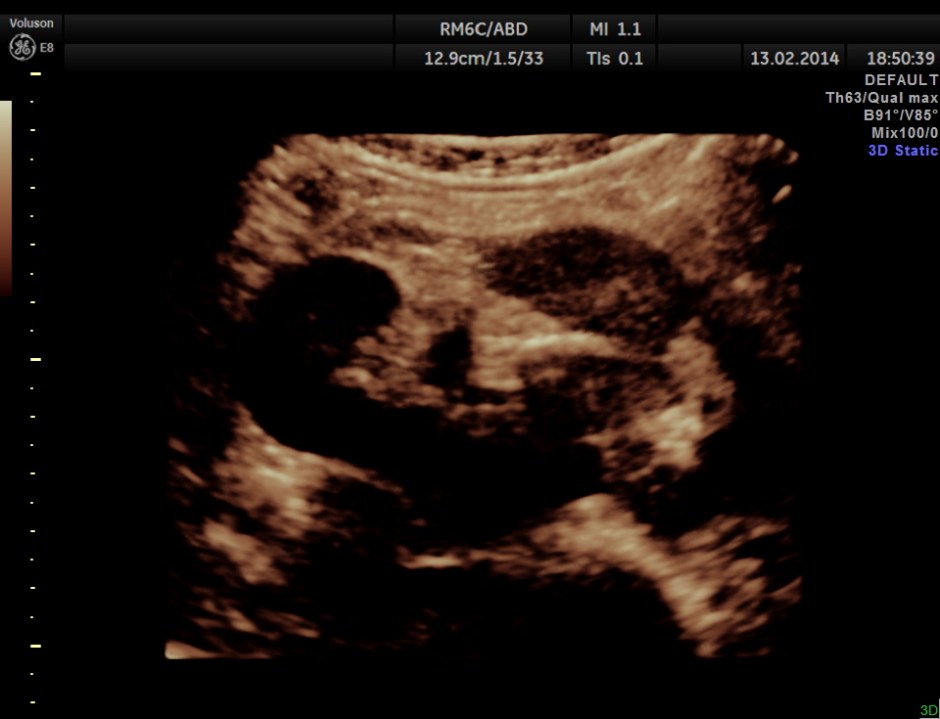

The following are the pictures of the kidney , which show the congenital horse shoe kidneys , placed ectopically in the pelvis. He had no urinary symptoms or low back ache at any time .

The right and left portions of the horse shoe are shown separately below

some of the reconstructed images are given below.